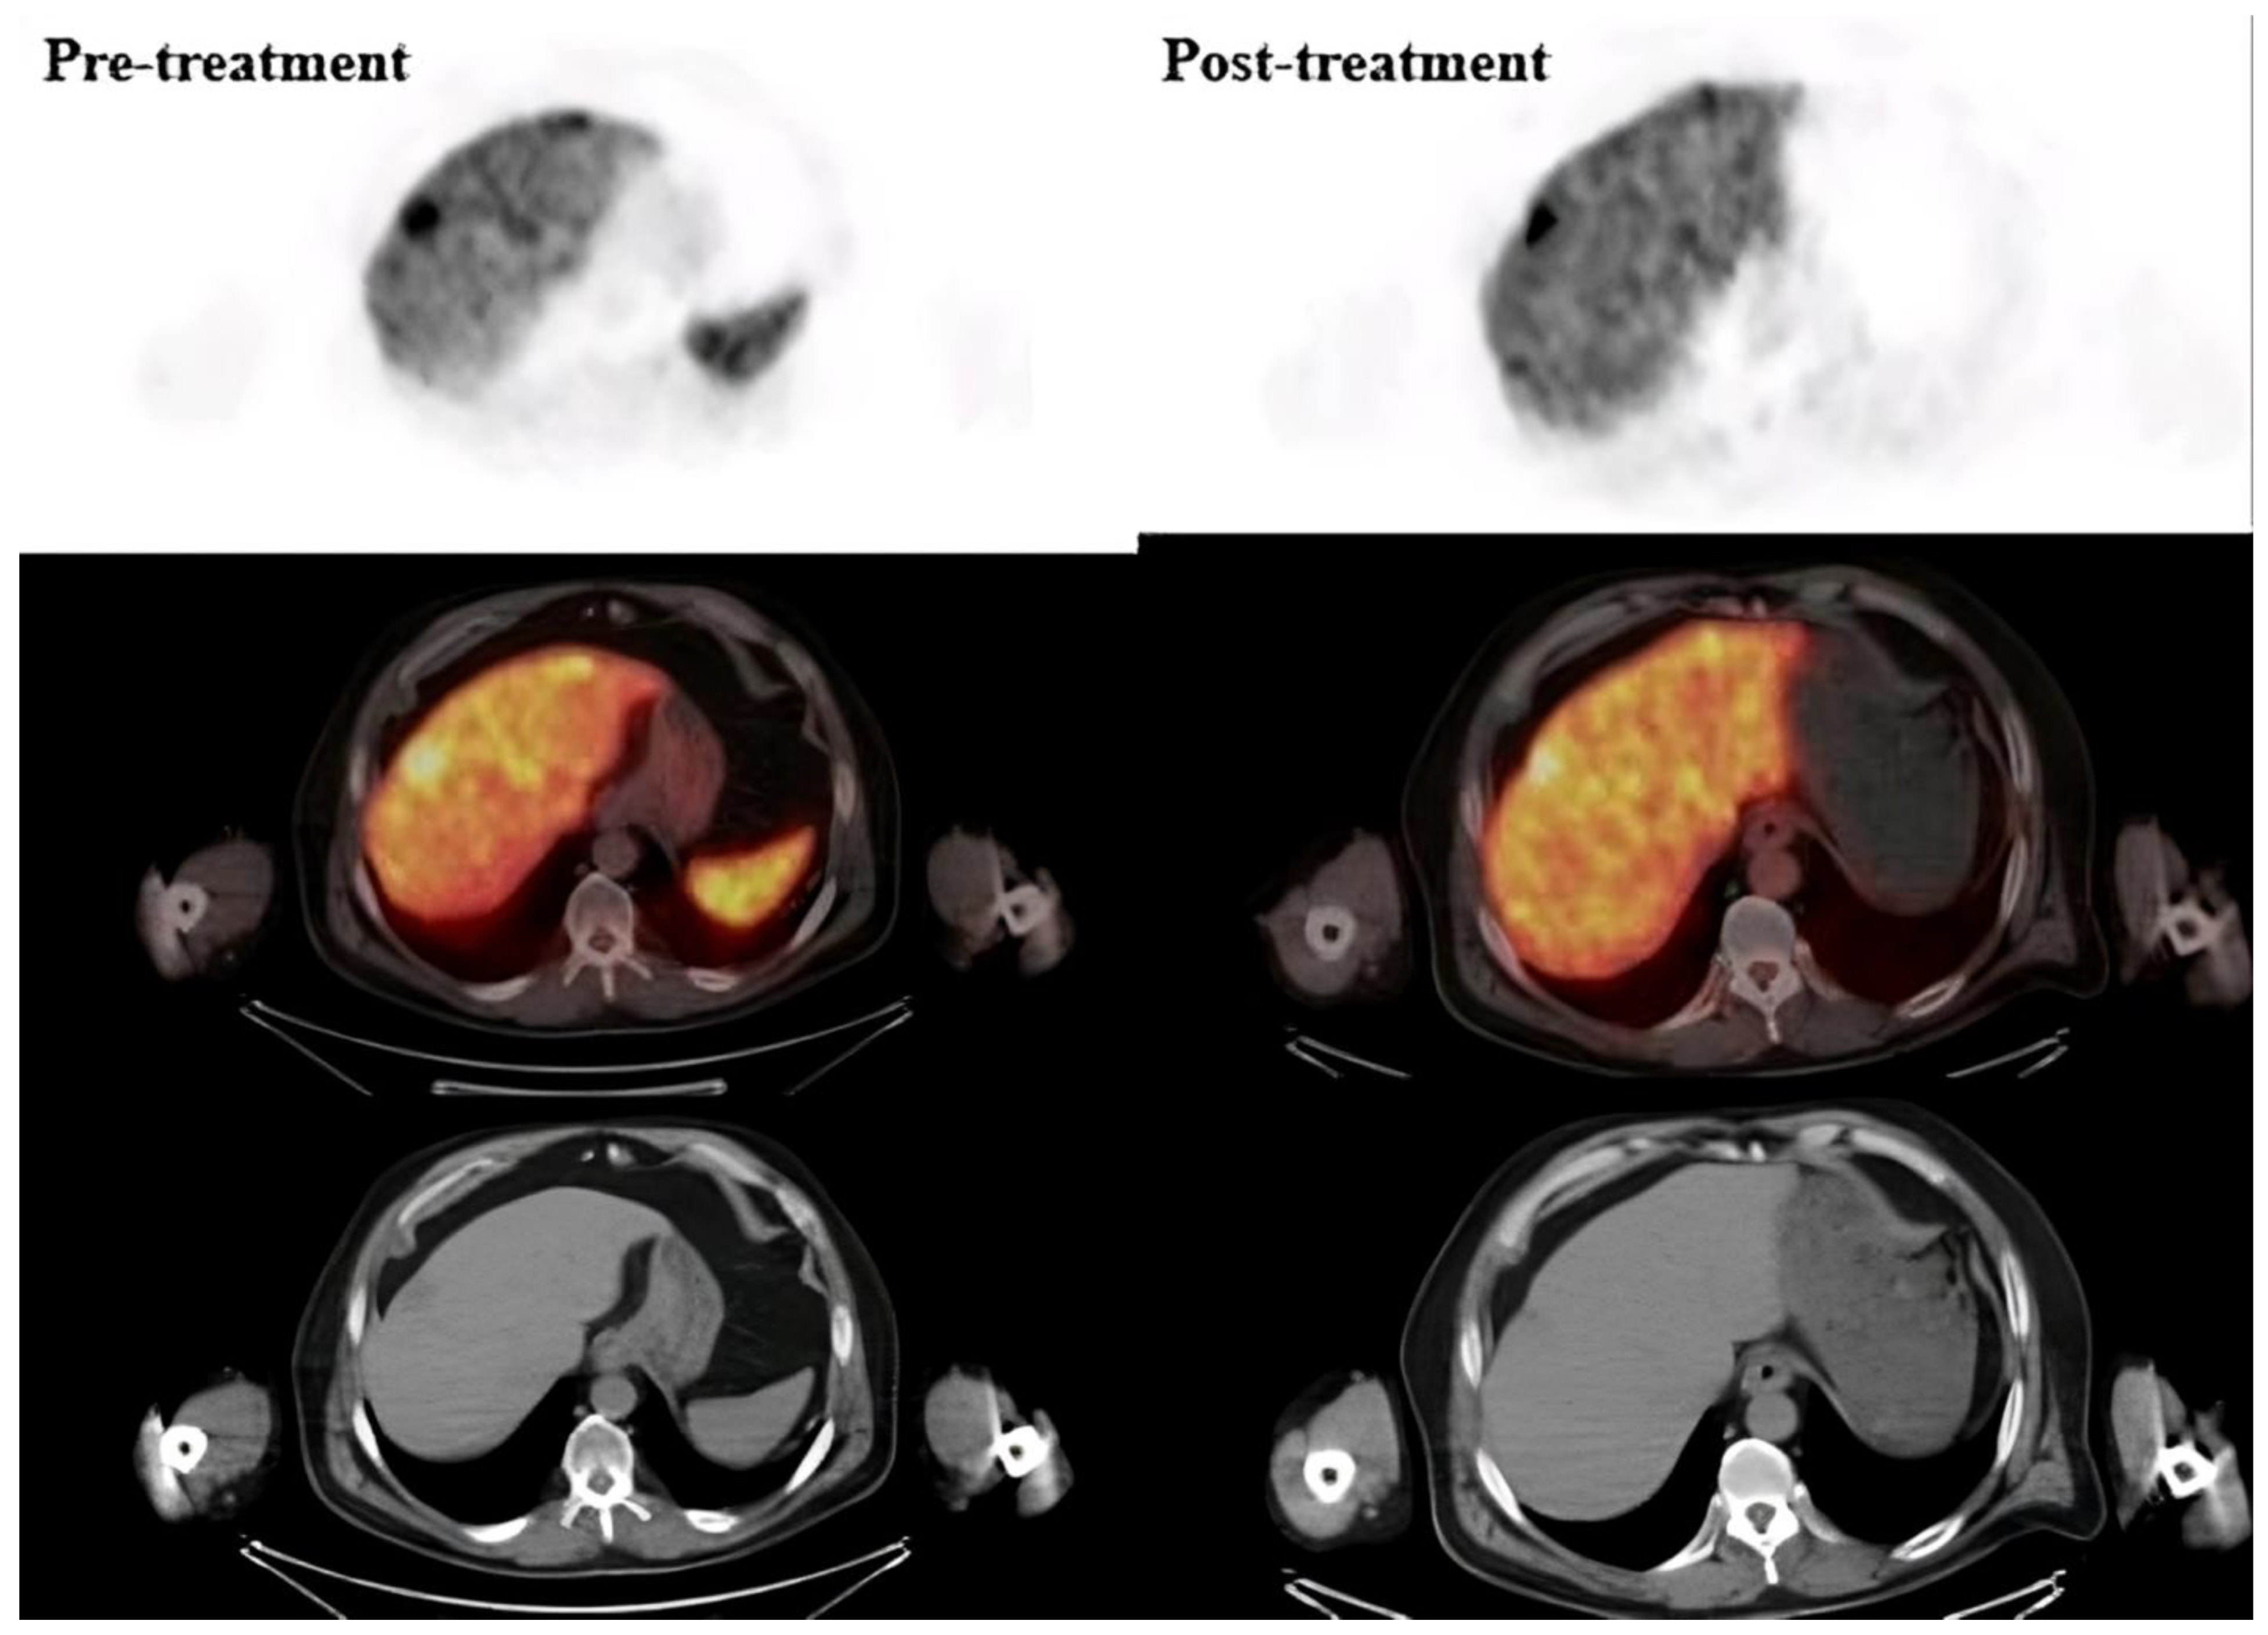

Figure 2. The pre-and post-treatment Ga-68 PSMA PET/CT images of a representative patient. The pre-treatment image shows liver lesions with high PSMA uptake (SUVmax: 60–68), indicating significant metastatic involvement. The post-treatment image, obtained after two cycles of Lu-PSMA-617 therapy, demonstrates a reduction in both lesion size and molecular activity, with a corresponding decrease in SUVmax values (SUVmax: 30–35).